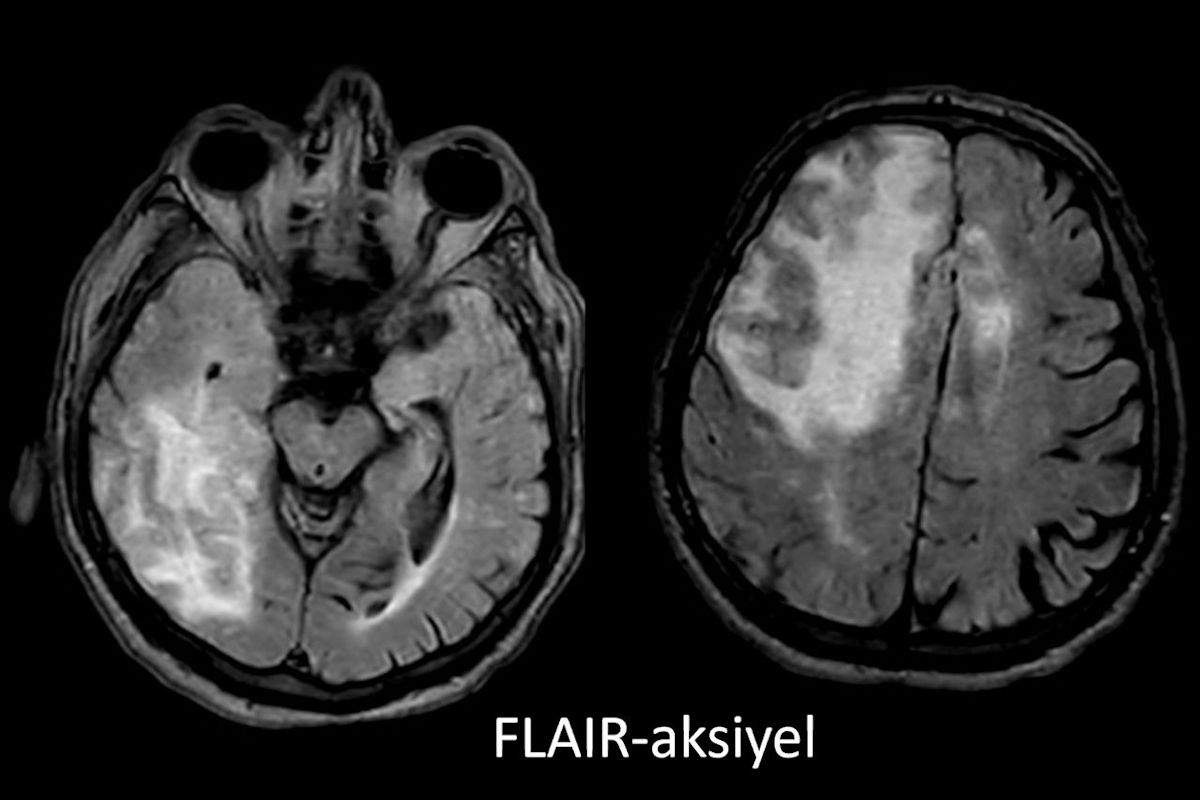

- A) Aksiyel planda FLAIR sekansta asimetrik kortiko-subkortikal vazojenik ödemi düşündüren yüksek sinyalli hafif ekspansil lezyonlar (turuncu ok).

- Difüzyon kısıtlılığının olmaması, leptomeningeal kontrastlanma, FDG-PET’te düşük aktivite, GRE sekansta yaygın hemosiderin kalıntılarının eşlik etmesi ile karakterizedir.

- 40 yaş üzeri bilinç bozukluğu, davranış değişikliği, fokal nörolojik bulgular, bulguların akut intrakraniyal kanama ile doğrudan ilişkilendirilmemesi, subkortikal beyaz cevhere uzanan asimetrik unifokal ya da multifokal kortiko-subkortikal ödemli lezyonlara serebral mikro/makrokanama, superfisiyal siderozisin eşlik etmesi halinde mutlaka düşünülmelidir.